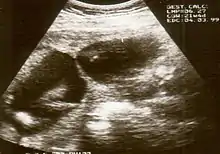

Diagnosis

The diagnosis of constriction ring syndrome can be confirmed with an ultrasonography. The clinical manifestations can be extremely variable. It could be a single or multiple manifestation. This can be confirmed at the end of the first trimester or at the beginning of the second trimester.[13] But not every patient will be diagnosed at that moment, most will get this diagnosis at birth.

Individual strands are small and hard to see on ultrasound, so bands are detected indirectly because of the constrictions and swelling upon limbs or digits. Misdiagnosis is also common, so if there are any signs of amniotic bands, further detailed ultrasound tests should be done to assess the severity. 3D ultrasound and MRI can be used for more detailed and accurate diagnosis of bands and the resulting damage/danger to the fetus.